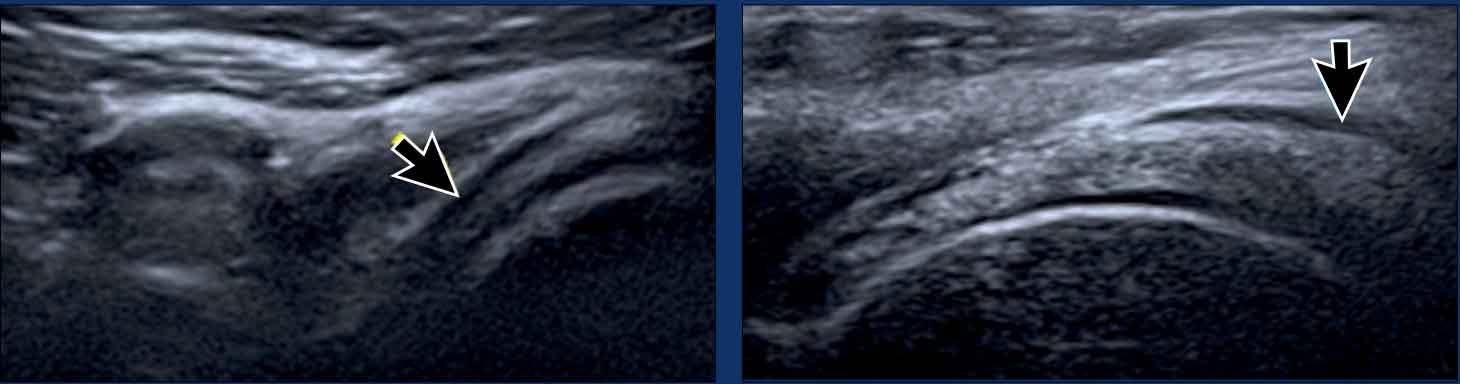

Bursitis

Khoang thanh mạc bình thường bị xẹp và

hầu như không thể phân biệt được bằng siêu âm (mũi tên).

Viêm túi thanh dịch cấp tính biểu hiện trên siêu âm là

sự giãn nở của túi thanh dịch (mũi tên vàng).

Viêm túi thanh dịch mạn tính có thể

thấy thành dày (mũi tên trắng).